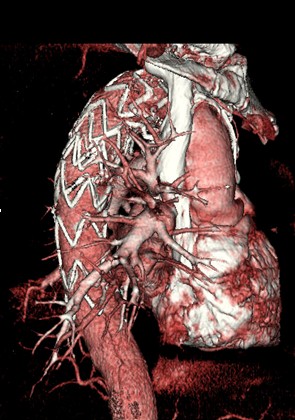

1、全身血管成像:该机扫描覆盖范围广,短时间内完成检查,多种后处理分析软件能显示各血管细小分支,可清晰显示动脉瘤、血管畸形、血管狭窄、动脉粥样硬化斑块、血管闭塞、主动脉夹层、肿瘤增生血管等。